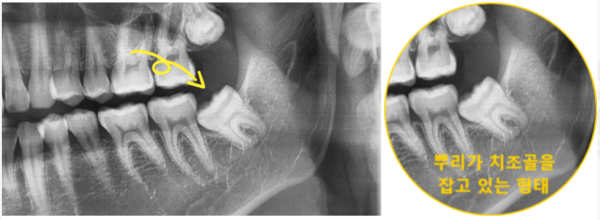

826fd3851ccac24696fbdfce7325926d_1697774664_5877.png

실제로 왼쪽 어금니쪽이 욱신욱신 하셨다고도 하셨는데요.

파노라마 사진으로 확인해보니 왼쪽 아래쪽 어금니가 매복형태로

발치가 어려운 형태로 맹출되어있었습니다.

You said that your left molar was throbbing.

I checked the panorama picture and found that the lower left molar was in the shape of an ambush

It was ferocious in a form that was difficult to extract.

826fd3851ccac24696fbdfce7325926d_1697774670_0313.png

이부분의 통증이 아주 심해서 잠도 못자겠다고 하셨는데요.

빠른 발치가 필요하신 상황이었습니다.

해당 부분을 확대하여 보면, 뿌리가 뼈를 움켜지고있는 형태여서 발치가 쉽지 않아보였습니다.

저희 성남치과 더서울치과에서는 이러한 고난이도의 사랑니발치를

꾸준히 해 오고 있기 때문에 이날 지체하지않고 바로 발치하기로 하였습니다.

The pain in this area is so severe that you can't even sleep.

You needed a quick extraction.

If you zoom in on that part, it didn't look easy to extract because the roots were gripping the bones.

Seongnam Dental Clinic, The Seoul Dental Clinic, provides these high-level wisdom teeth

Since we have been doing it steadily, we decided to remove it right away without delay on this day.